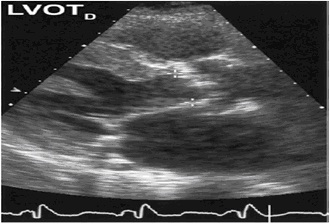

L’esame strumentale piu’ indicato per fare diagnosi certa di stenosi aortica e’ rappresentato dall’Ecocardiogramma:

• Rileva la valvulopatia e ne quantifica la severità

• Definisce la sede (valvolare, sotto o sopravalvolare)

• Identifica eventuali patologie concomitanti (valvolari e non)

• Valuta la funzione sistolica ventricolare sinistra

• Valuta le ripercussioni sul circolo polmonare

• Calcola i gradienti transvalvolari massimo e medio

• Calcola l’area valvolare

• Misura il rapporto tra velocità registrate nel LVOT ed all’orifizio aortico